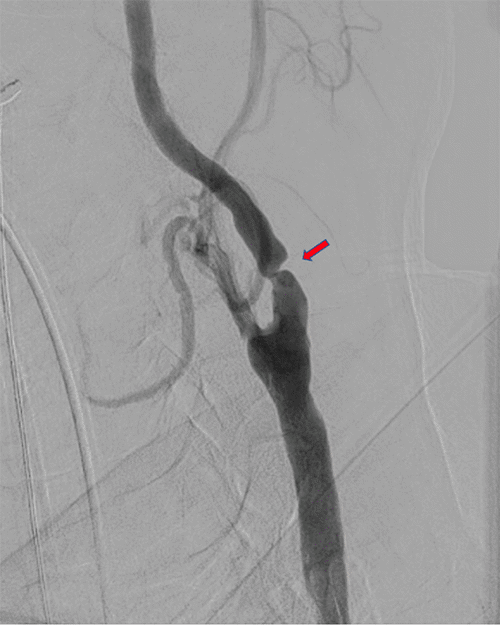

After expedited preoperative evaluation and medical optimization, the patient was taken to the hybrid suite for left TCAR under general anesthesia with cerebral oximetry. Carotid angiogram via direct proximal cervical common carotid artery exposure demonstrated severe focal ICA stenosis, corresponding with preoperative imaging (Figure 2A). After systemic anticoagulation and initiation of flow reversal via right femoral vein access, angioplasty of the left ICA was performed with a 5 × 20 mm balloon, followed by deployment of a 10 × 40 mm ENROUTE Transcarotid Stent (Silk Road Medical, Sunnyvale, CA) across the stenosis extending from the distal common carotid to the mid-ICA (in order to incorporate the ICA dissection). Completion angiogram demonstrated successful stent deployment with widely patent common, internal, and external carotid arteries (Figure 2B). The patient awoke without neurologic deficits. After surgery, he reported no headaches or further episodes of amaurosis fugax or other neurological events. Following one more day of blood pressure control management, he was discharged home with a prescription for clopidogrel. A plan was made for elective Right TCAR after a minimum of six weeks. The decision for a six-week interval was based on surgeon preference. While there is no conclusive data supporting simultaneous carotid interventions, many surgeons concur that waiting for recovery and monitoring hemodynamic and neurological function afterward may be safer, particularly for high-risk patients with severe stenotic lesions prone to reperfusion syndrome.

Figure 2. Left Carotid Angiogram During TCAR Procedure Before A) and After B) Angioplasty and Stent Deployment. Published with Permission

A.

B.